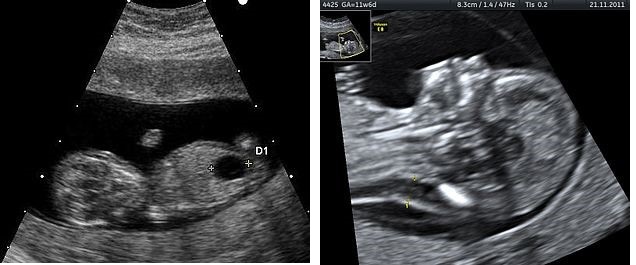

Есть небольшой шанс, что специалист обнаружит синдром дауна на узи. К ним относятся увеличение объема кожи в области затылка, уменьшение размера бедра или кисты в головном мозге. По словам врачей, синдром дауна по узи нельзя диагностировать. Это обследование не выявит ожидаемый риск трисомии 21.

Ультразвуковое изображение на 20 неделе может использоваться для скрининга синдрома Дауна у плода.

1 Ультразвук плода с большим пузырем 2 Увеличенный NT и отсутствующая носовая кость у плода в 11 недель с синдромом Дауна

Эхопризнаки синдрома дауна на узи, которые указывают на повышенный риск, когда наблюдаются во втором триместре беременности.

Плод с синдромом дауна может иметь небольшую или отсутствующую носовую кость, большие желудочки мозга, толщину затылочной складки и ненормальную правую подключичную артерию.